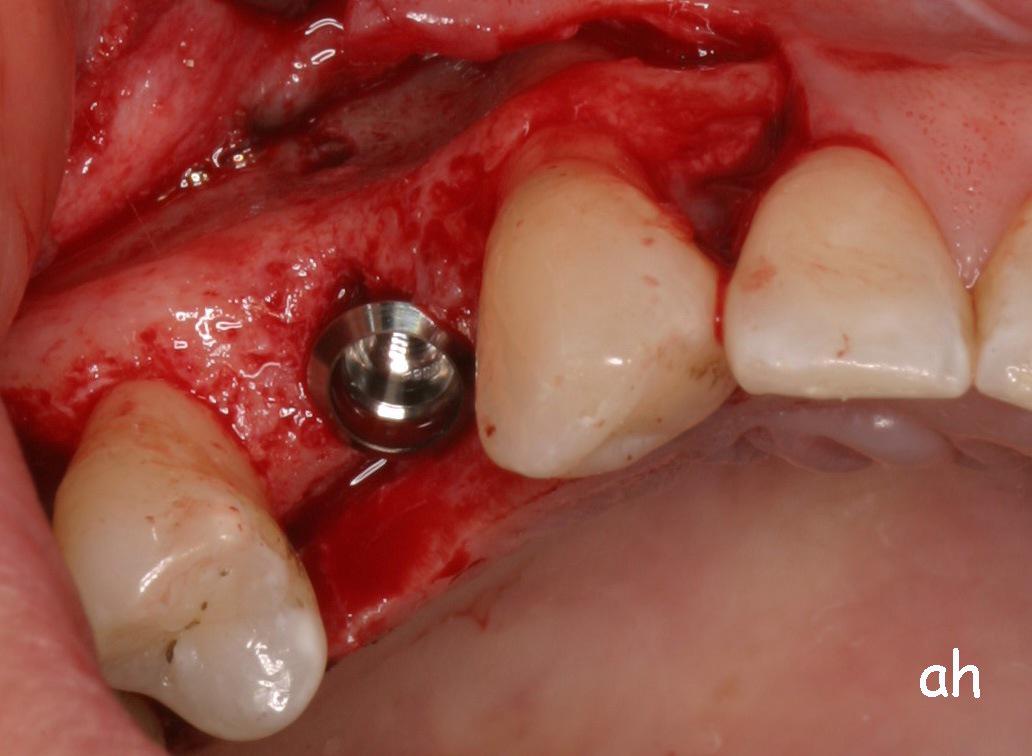

Exemple 1: Ce patient a perdu son incisive centrale gauche lors d'un accident. Un implant a été posé

Exemple 1: L'implant remplace la racine de la dent manquante

Exemple 1: L'implant s'est intégré dans l'os, une empreinte est effectuée. Le laboratoire peut réaliser la couronne en céramique.